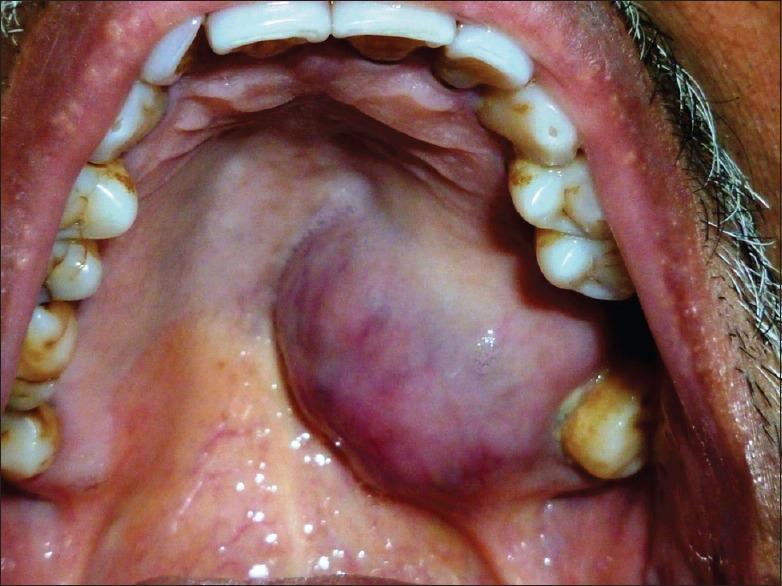

Polymorphous low-grade adenocarcinomas (PLGA) are distinctive salivary gland neoplasms, with an almost exclusive propensity to arise from the minor salivary glands. PLGA frequently manifests as an asymptomatic, slow-growing mass within the oral cavity, which must be separated from adenoid cystic carcinoma and benign mixed tumor for therapeutic and prognostic considerations. We report a case of a 67-year-old male, who presented with a long-standing mass in the palate. This lesion was diagnosed as PLGA based on histopathological findings, which was further confirmed by the immunohistochemical marker.